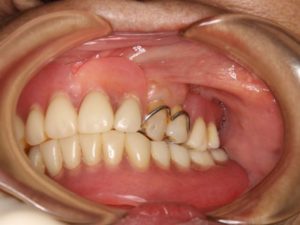

〈治療前〉

治療前は上顎に2本、下顎に1本の歯が残っていて、残っている歯に金属のバネをかけてクラスプ義歯を使用されていました。当院へは使用している義歯であまり噛めないとご相談を受けました。

この時の口元は左右の唇が対照的ではないところや下唇の方が前に膨らんでいるところが気になります。